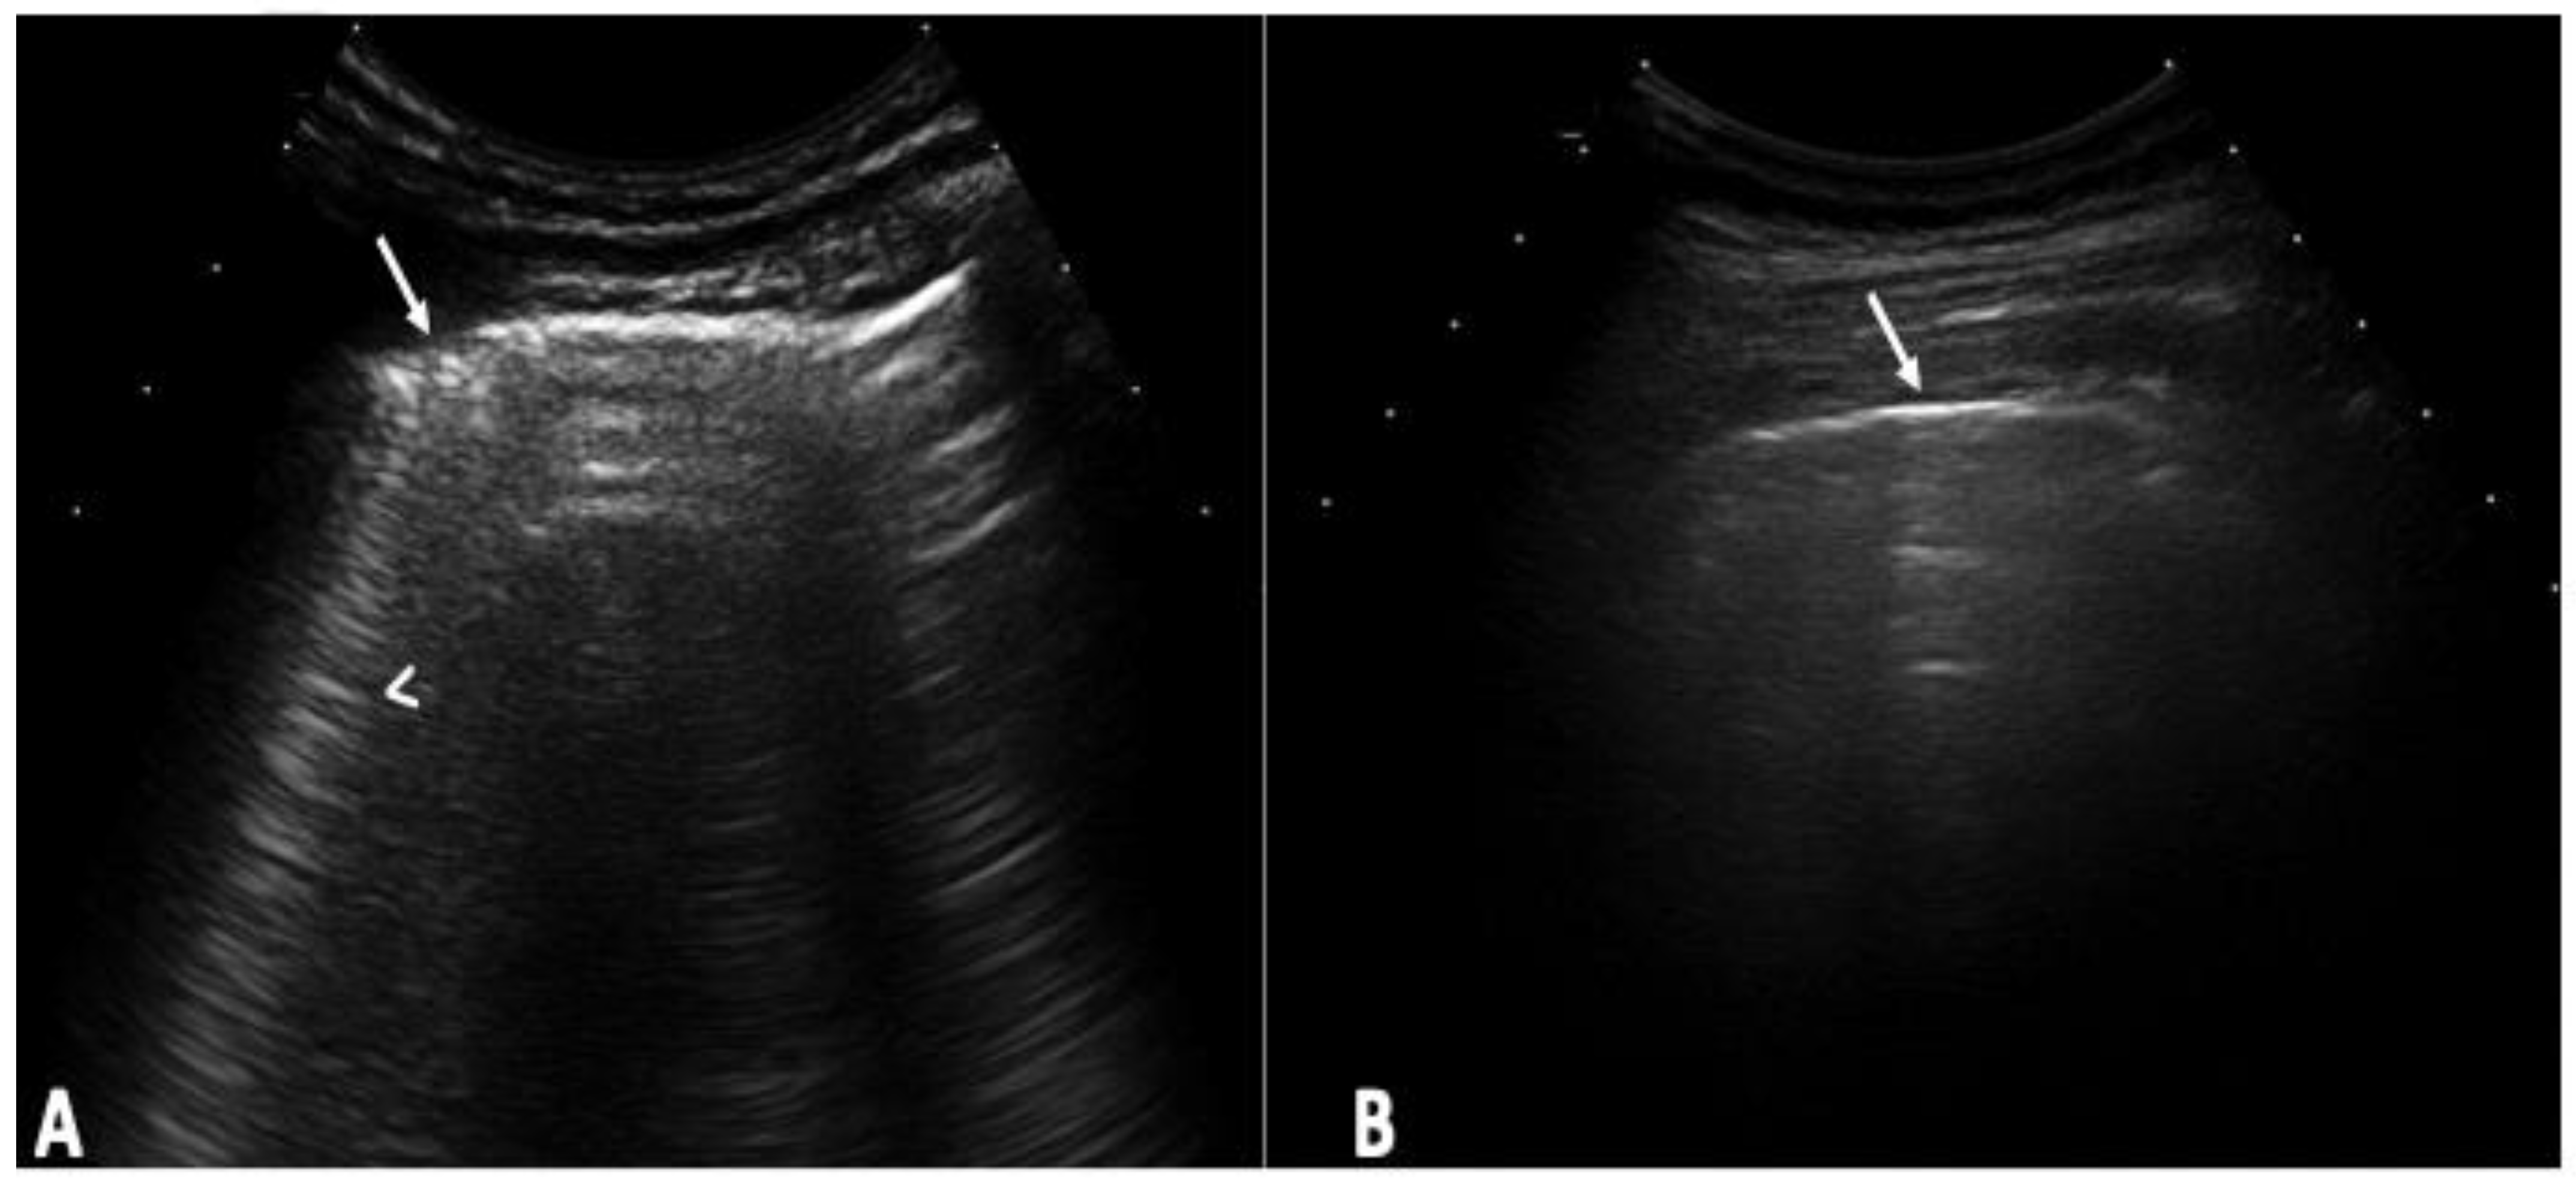

- Pinal-Fernandez, I.; Pallisa-Nuñez, E.; Selva-O’Callaghan, A.; Castella-Fierro, E.; SimeOn-Aznar, C.P.; Fonollosa-Pla, V.; Vilardell-Tarres, M. Pleural irregularity, a new ultrasound sign for the study of interstitial lung disease in systemic sclerosis and antisynthetase syndrome. Clin. Exp. Rheumatol. 2015, 33, S136–S141. [Google Scholar]